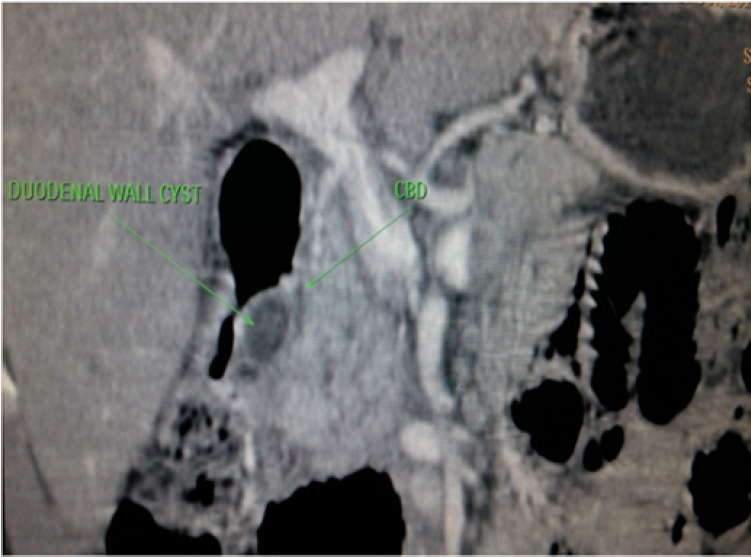

A 40yr old male with history of repeated episodes of the abdominal pain with nausea, vomiting and weight loss of 3 kg in past 4 weeks was referred to radiology department for CECT abdomen. The patient was a smoker with history of alcohol abuse. His serum amylase and lipase levels were raised. CECT abdomen of the patient was done which showed enlargement of the pancreatic head with loss of fat planes between the duodenum and the pancreas. Ill defined hypo enhancing soft tissue was seen in the pancreaticoduodenal groove with thickened medial wall of the duodenum.There was presence of duodenal wall cyst along the medial border leading to the narrowing of the lumen of duodenum. The main pancreatic duct was dilated. CBD was normal in its caliber.Body and tail of pancreas was normal in size and post contrast CT attenuation.Based on these findings diagnosis of the segmental form of groove pancreatitis was made. Diagnosis of pure form of groove pancreatitis was excluded because of involvement of the pancreatic head.

Other differential diagnosis that was considered was of pancreatic head malignancy ,but imaging finding of bulky head of pancreas, thickened medial wall of duodenum, duodenal wall cyst, dilated pancreatic duct, well maintained peripancreatic vessels without any signs of thrombosis and infiltration were more in favour of diagnosis of groove pancreatitis.

Figure 2: Coronal CECT Image Shows Duodenal Wall Cyst Leading to Narrowing of the Lumen of Duodenum, Enlarged Pancreatic Head and Relatively Hypoenhancing Tissue in the Pancreaticoduodenal Groove